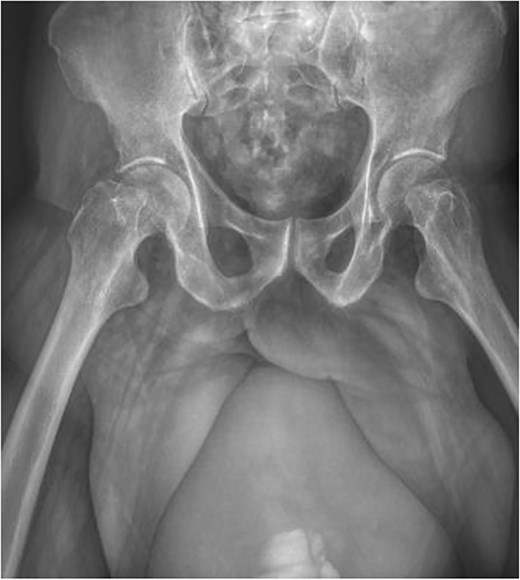

A non-contrast pelvic computed tomography (CT) scan was performed to evaluate a palpable right inguinal mass. The CT revealed an aponeurotic defect in the right inguinal region with protrusion of the urinary bladder into the right inguinal canal, completely lodging in the scrotal sac. This finding was associated with increased scrotal volume, striations of the periscrotal fat, and thickening of the scrotal wall by 25 mm. Significant dilation of the renal collecting system was also observed, measuring 40 mm on the right side and 62 mm on the left, with an increase in the diameter of the ureters. The bladder presented dimensions of 240 × 173 × 194 mm with a volume of 4212 mL, completely full and entirely located within the right scrotal sac. The findings indicate the presence of a right inguinoscrotal vesical hernia with bilateral dilation of the pelvicalyceal system, possibly exacerbated by maximum bladder filling (Fig. 3a–d, h, and i).

Simple abdominopelvic CT scan slices showing significant dilation of the renal collecting system, measuring 40 mm on the right side and 62 mm on the left, with an increase in the diameter of the ureters (a–c), an aponeurotic defect in the right inguinal region with protrusion of the urinary bladder into the inguinal canal (d–f), and the bladder completely full and entirely located within the right scrotal sac (g–i).